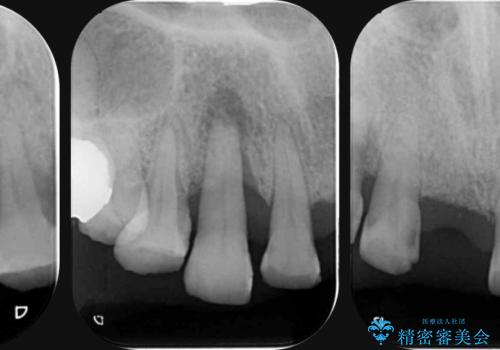

- 前歯を噛みしめにより失い、さらに犬歯もグラグラになり全く噛めなくなり改善を求めて来院されました。

過度な力がかかり周囲の骨に高度な吸収が見られた犬歯は抜歯し、機能・審美性の回復をより咬合力に対して抵抗力のあるブリッジ補綴にて対応します。